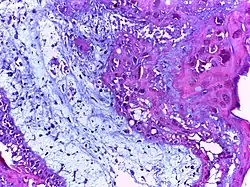

Foreign body granuloma | Granulomatous reaction to keratin characterized by foreign body giant cells and chronic inflammatory cells. | Category: Histopathology of foreign body granuloma | Foreign body granuloma, silicone granuloma |